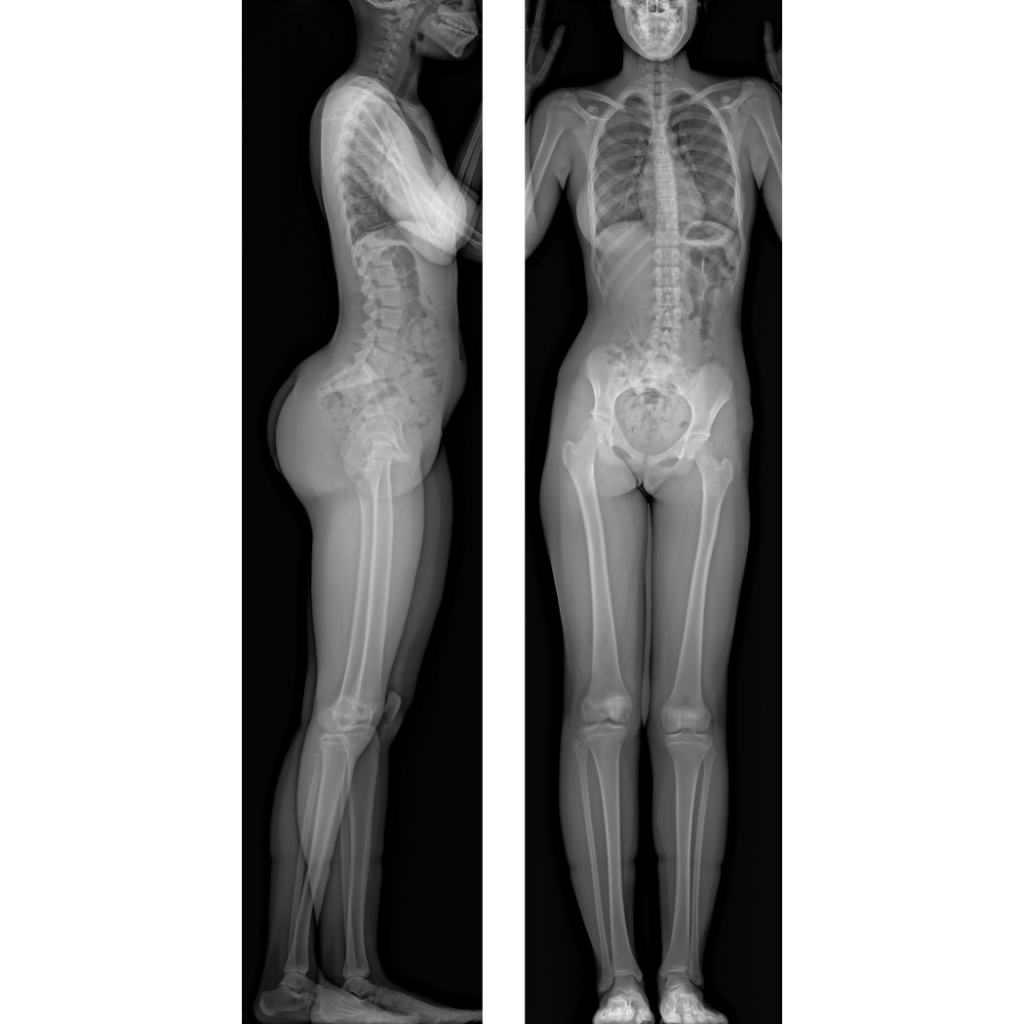

EOSedge is a precise, low dose imaging system that delivers full body, high-quality images covering the full set of musculoskeletal and orthopedic exams.

This next generation solution captures fully functional 2D/3D biplanar images in seconds, using a high-resolution photon-counting detector for outstanding image quality for a broad range of patients.

Its innovative design minimizes radiation exposure following ALADA* principle to give providers the insight they need to make well-informed clinical decisions at each point of patient care.

EOSedge uses new Flex Dose™ technology to modulate radiation throughout scans using body morphology. Flex Dose delivers up to an 80% overall radiation reduction compared to the same acquisition without Flex Dose5.